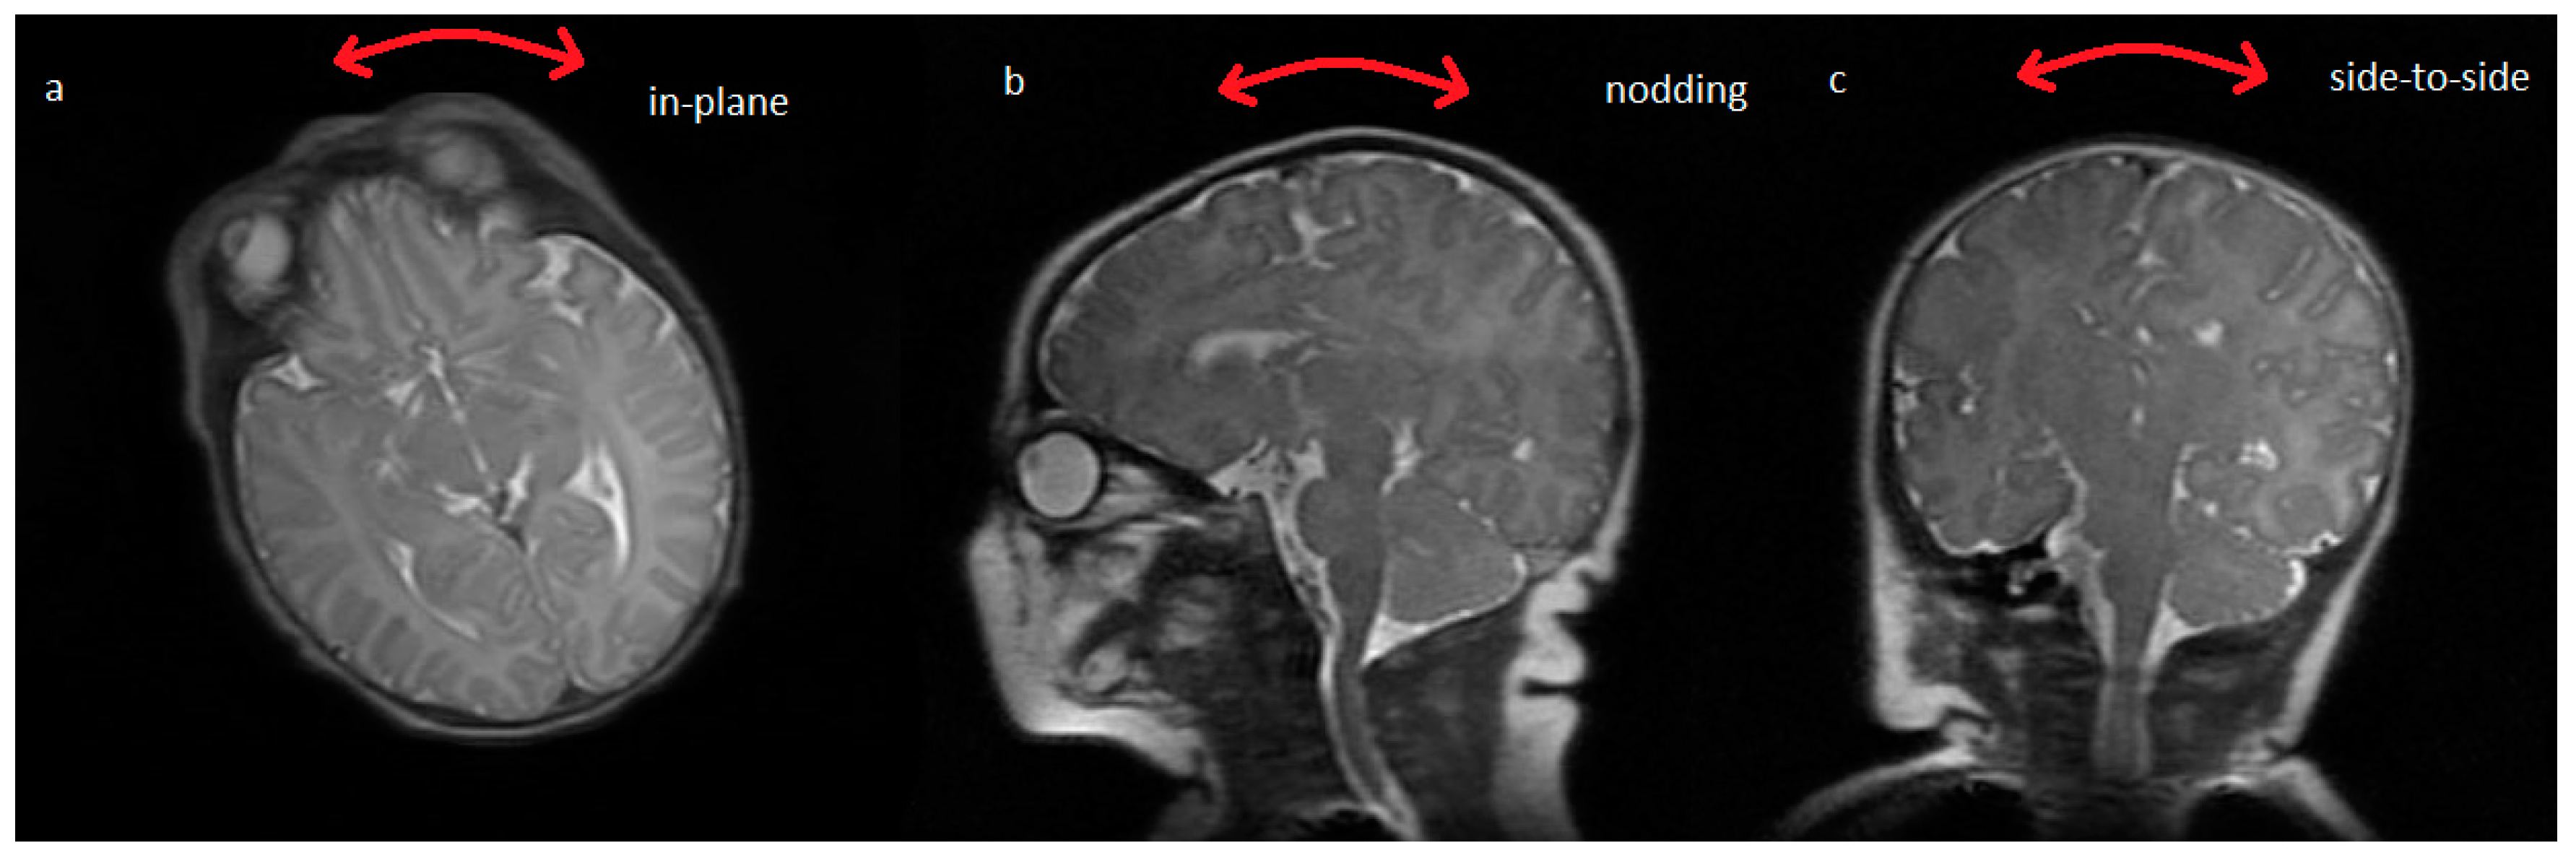

Nodding and side-to-side motions are also important in creating artifacts on neonatal MRI but in this feasibility study we chose to restrict the motion to just one dimension using axial image acquisition only. Different modes of one-dimensional motion are illustrated in Figure 2 [11]. By choosing either sagittal or coronal image planes, head nodding backwards and forwards or side to side could also be corrected using this method.

Figure 2. Different modes of neonatal head motion which could be corrected using one dimensional angular information from the wireless accelerometer. Extension to oblique orientations and to full 3D correction should also be possible but requires further work on the reconstruction algorithm.